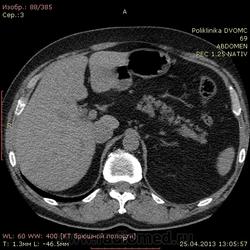

Уважаемые коллеги КТ-шники 2 часа ищу холедох, все перерыл, пересравнивал. Четко его так и не нашел, а в книжках пишут(можт обманывают?), что должен быть виден всегда. В сязи с этим огромная просьба: помогите!!!! и ткните, наконец, стрелкой в то место куда надо смотреть...спасибо.

Ткнуть, говорите? Это можно. Вспоминаем анатомию: гепатиколедох расположен в печеночно-двенадцатиперстной сваязке кпереди от воротной вены.